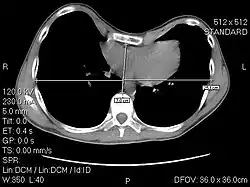

The Haller index, created in 1987 by J. Alex Haller, S. S. Kramer, and S. A. Lietman,[1] is a mathematical relationship that exists in a human chest section observed with a CT scan. It is defined as the ratio of the transverse diameter (the horizontal distance of the inside of the ribcage) and the anteroposterior diameter (the shortest distance between the vertebrae and sternum).[2]

- distance 1 is the distance of the inside ribcage (at the level of maximum deformity or at the lower third of the sternum)

- distance 2 is the distance between the sternal notch and vertebrae.